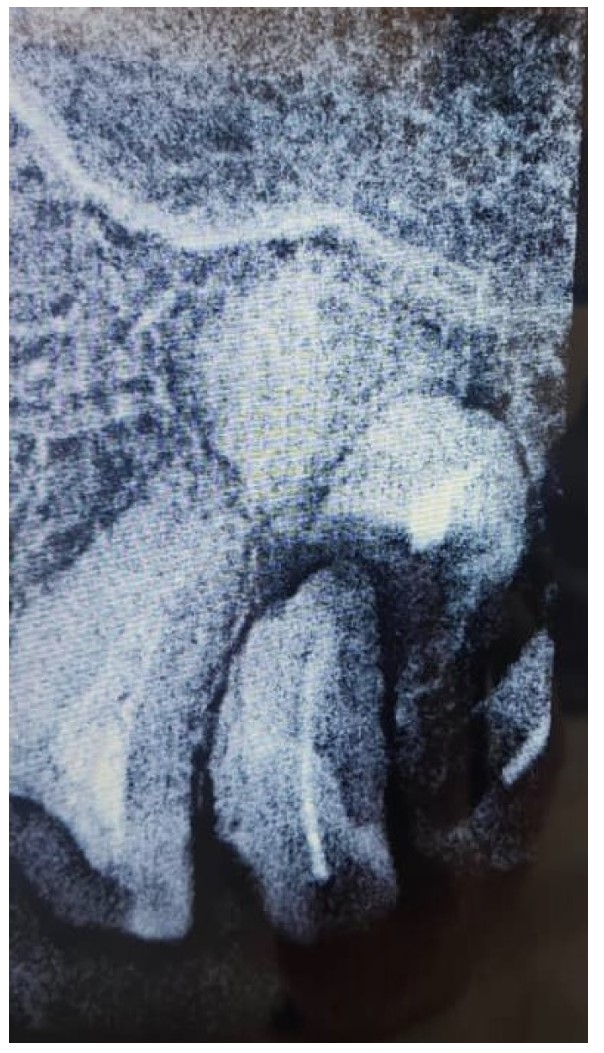

Periapical view of the maxillary molar region showing unrestorable roots, as well as a radiopaque lesion on the periapical plane that was not noticed during the preoperative radiograph.

Preoperative scan showing the location of the lesion noted when reviewing scans after implant failure.